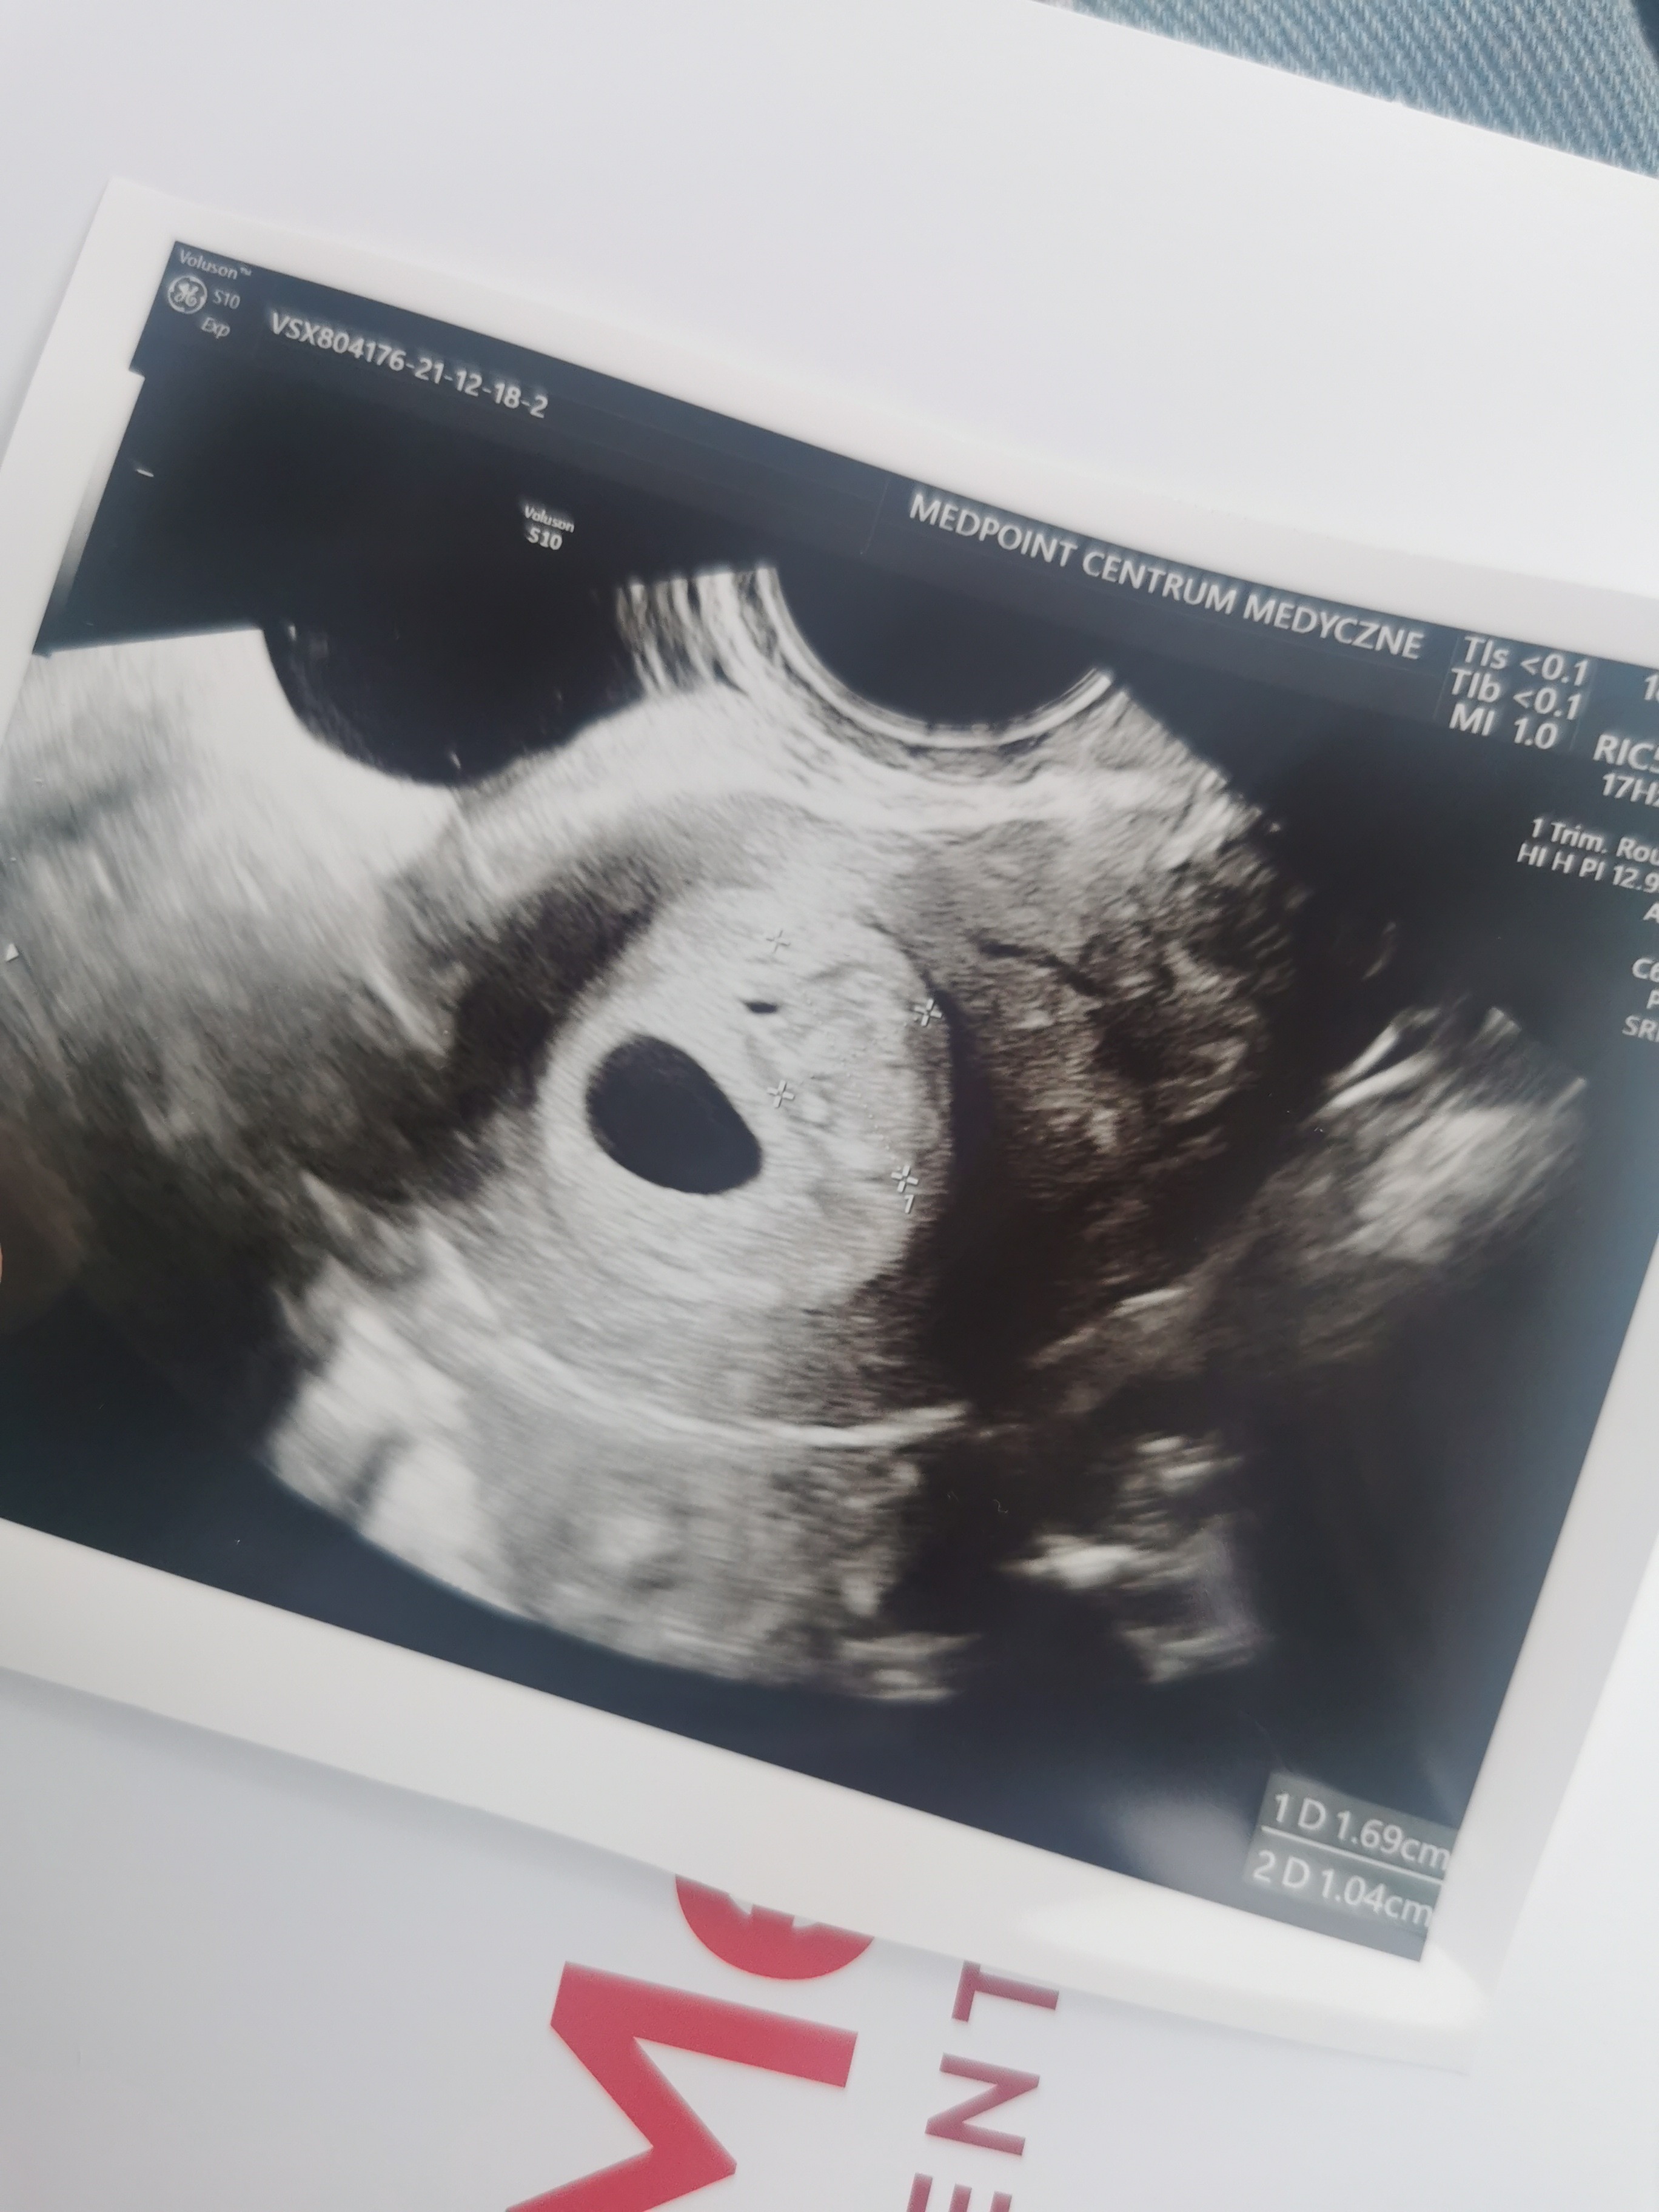

Hej dziewczyny.bylam wczoraj na usg. Mam wyliczone dokladnie 6 tyg wczoraj i mamy pecherzyk 1.1,cialko zolte i zarodek 3.3 z zaczynajacymi sie tlic komorkami i to bylo wlasnie tworzace sie serduszko . Jedyny problem to maly krwiak 1.7x1, ale nie przylega do pęcherzyka i jest dość jasny na obrazir wiec prawdopodobnie sie wchlania. Mialyscie podobny obraz usg? Z zalecen tylko progesteron raz dziennie i nie dzwigac, oszczedzac sie.

• IMG_20211218_133342.jpg

IMG_20211218_133342.jpg

957,7 KB · Wyświetleń: 152